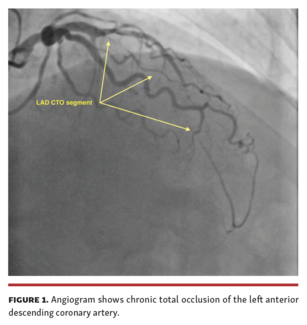

Omer Dogan, MD; Cuneyt Kocas, MD; Hasan Ali Barman, MD; Irfan Sahin, MD

In this case, we aimed to present a case in which TIMI 0 flow was observed in the LAD after unsuccessful PCI attempt, but was left to recover with the investment procedure and TIMI 3 flow was detected in the control angiogram.